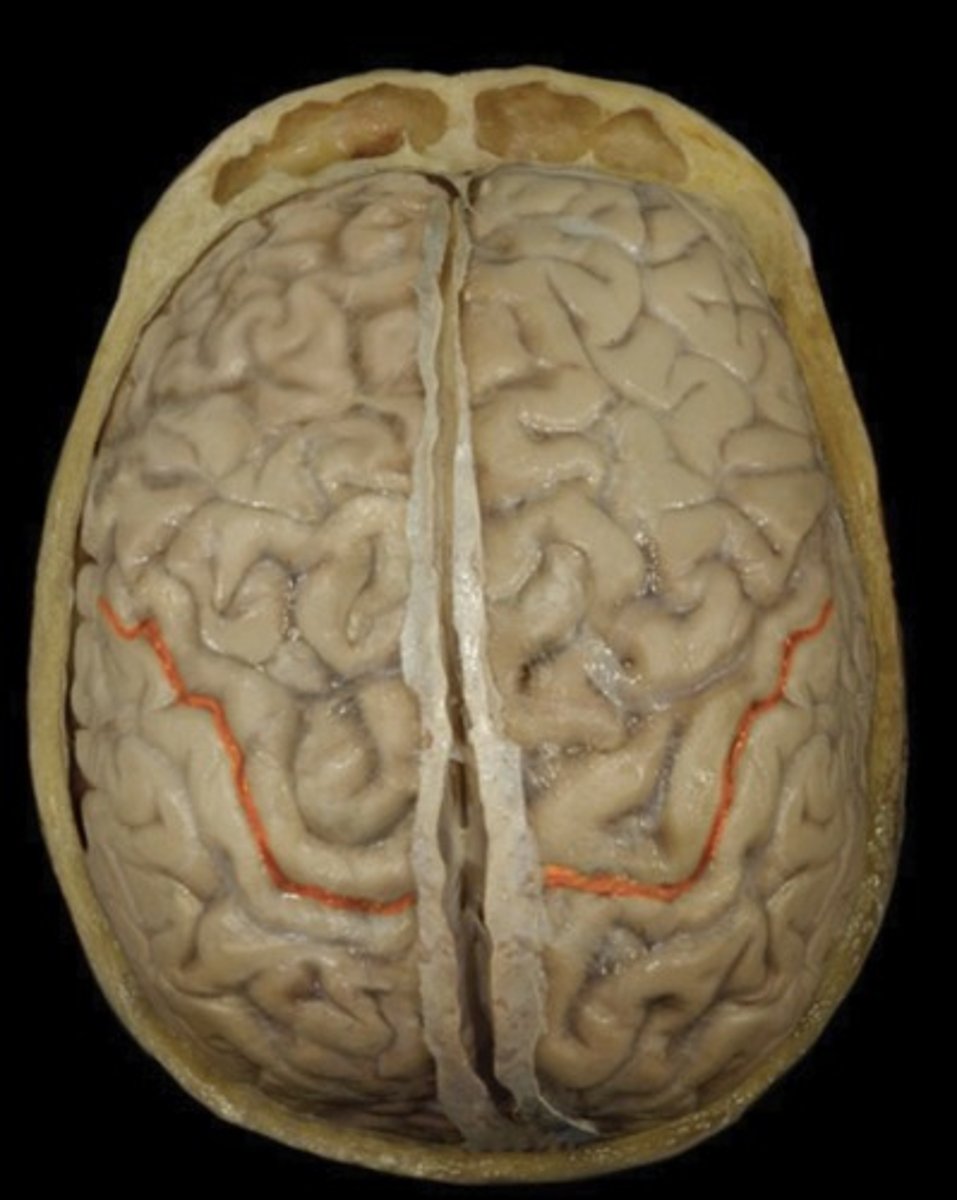

Central Sulcus

Name this structure

Precentral Gyrus (superior view)

Name this structure

Postcentral Gyrus (superior view)

Name this structure

Frontal Lobe (superior view)

Name this structure

Occipital Lobe (superior view)

Name this structure